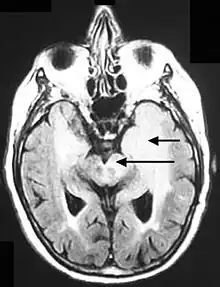

Axial fluid-attenuated inversion recovery MRI image demonstrating tumor-related infiltration involving lenticular nuclei (Arrow).